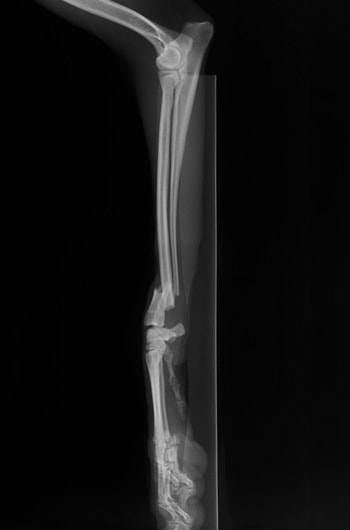

症例3:キルシュナーワイヤーのピンニングによる整復

ペルシャ猫 11ヶ月齢 雄

他院にて左大腿骨遠位の成長板骨折(salter-harrisⅠ型)が認められており、治療相談を目的として来院。当院にて、キルシュナーワイヤーを用いたピンニングにより骨折部位の整復を行いました。術後の経過は良好で、現在も経過観察中です。

術前レントゲン

術後レントゲン